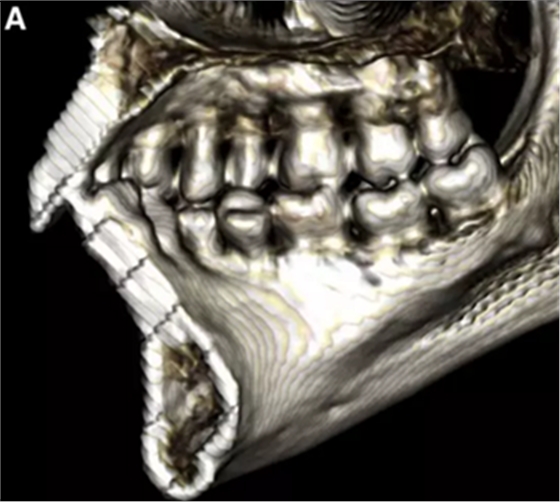

然而,CBCT成像也具有較大的限制:有限的分辨率,牙體組織的不準確表現(xiàn),以及當患者在咬合位或者完全牙尖交錯位CBCT掃描時,上頜骨和下頜骨牙齒之間發(fā)生的混合(圖1)。 這種混合使上頜骨與下頜骨牙齒的自動分離復雜化,并且由于咬合解剖結(jié)構(gòu)和細節(jié)的不準確而使人工分離變得困難。

圖1. 在CBCT中咬合時上頜牙齒和下頜牙齒咬合面的混合和咬合細節(jié)的喪失。